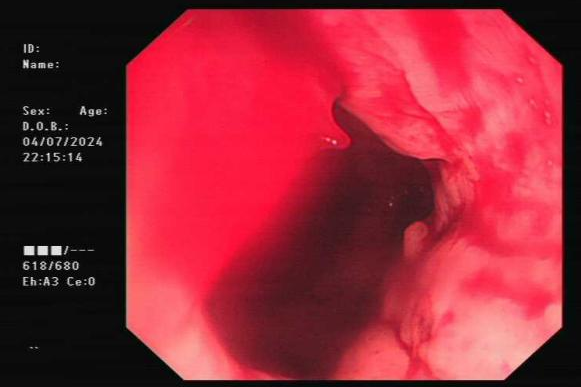

刘XX,男性,33岁,因“便血7小时”入院。入院后夜间患者突发解大量鲜血便,伴头晕、全身湿冷,当时测得血压为68/40mmHg,考虑消化道大出血、失血性休克。消化内科团队迅速给予补液抗休克、升压、生长抑素收缩内脏血管、止血对症处理,行急诊肠镜检查见结肠散在多处憩室并伴有活动性渗血,随即给予钛夹夹闭憩室,成功止血,对症治疗后患者已出院。

结肠憩室并活动性渗血

钛夹夹闭憩室成功止血